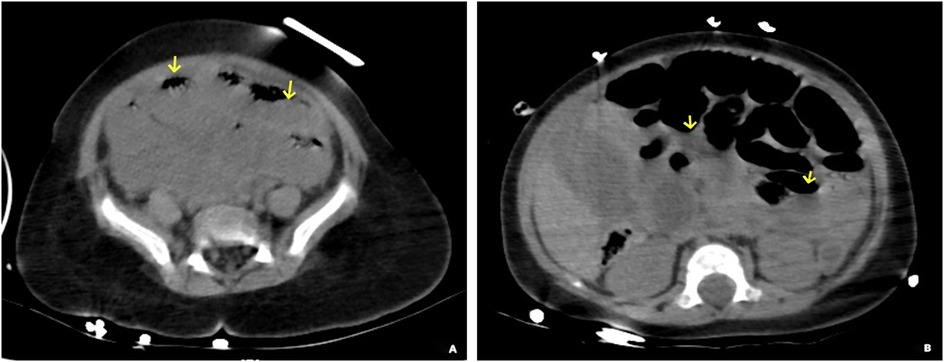

Congenital transmesenteric hernia, a rare internal hernia, is notoriously challenging to diagnose preoperatively due to nonspecific symptoms and inconclusive routine evaluations. In infants, early manifestations such as vomiting, irritability, and diarrhea often mimic acute gastroenteritis, leading to delayed recognition. Without timely intervention, progression to intestinal strangulation, necrosis, and shock significantly escalates treatment complexity and mortality risk. We report a case of a 6-month-old female infant with approximately 131cm of necrotic small bowel secondary to a giant transmesenteric hernia. This case illustrates the clinical trajectory, diagnostic pitfalls, and surgical management, highlighting the imperative for early suspicion and intervention. Critical analysis of this case underscores that prompt surgical correction is pivotal to mitigate morbidity and mortality in such scenarios. Enhanced clinician awareness of this condition and its subtle early signs could improve outcomes in pediatric patients.